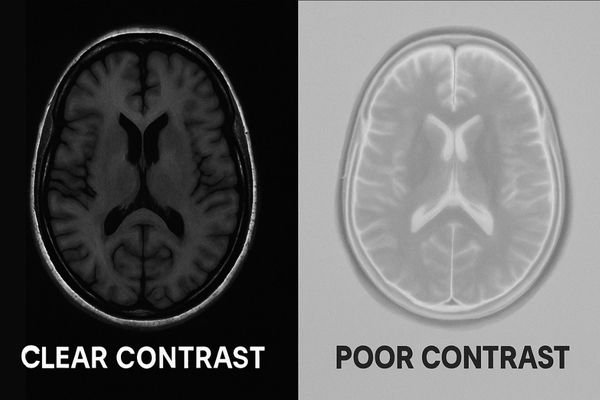

A monitor’s declining contrast ratio isn’t just a minor inconvenience; it directly impacts image clarity. For medical professionals, this degradation can obscure vital details, potentially affecting clinical decisions and patient care outcomes.

When a monitor’s contrast ratio declines, images appear washed out, and the ability to distinguish between subtle shades of gray or color diminishes significantly. This flattening of visual depth particularly compromises grayscale-heavy modalities like X-rays and CT scans, potentially leading to missed diagnoses or misinterpretations.

Contrast ratio defines a display’s ability to show the brightest whites and deepest blacks. A higher ratio means better differentiation of subtle grayscale steps and color nuances, crucial for detailed medical image interpretation.

Contrast ratio is a fundamental specification of any display, measuring the luminance difference between the whitest white (Lmax) and the darkest black (Lmin) a monitor can produce (Lmax/Lmin). In medical imaging, this isn’t just a technical number; it’s a direct determinant of how well a clinician can perceive fine details. A high contrast ratio1 allows for a wider gamut of distinguishable shades, making subtle variations in tissue density or structure more apparent.

For grayscale-dominant modalities2 like X-ray, CT, and MRI, which form the backbone of diagnostics, the ability to discern minute differences in gray levels is paramount. For example, our Reshin MD26GA 2MP or MD33G 3MP diagnostic monitors3 are designed with high contrast to ensure these subtle findings are not lost. A declining contrast ratio would compress these grayscale steps, making it harder to identify faint nodules, hairline fractures, or subtle edemas. Similarly, in color imaging, such as endoscopy or ultrasound, a robust contrast ratio helps preserve the vividness and separation of colors, aiding in the identification of tissue vascularity, inflammation, or other chromatic cues. Our surgical displays, like the Reshin MS275P 27" 4K Surgical Monitor, leverage high contrast to provide surgeons with clear, distinct views of the operative field.